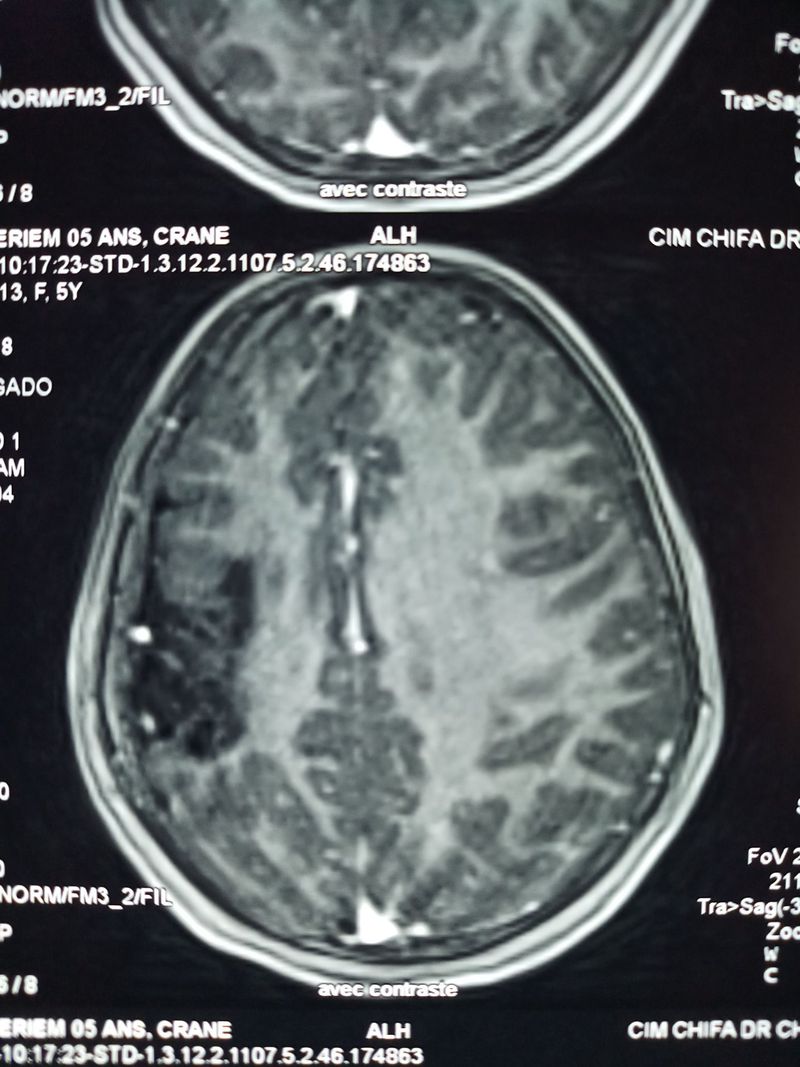

5 year-old-girl with hemiparesis

It is a rare syndrome

The diagnosis is: Dyke-Davidof-Masson syndrome